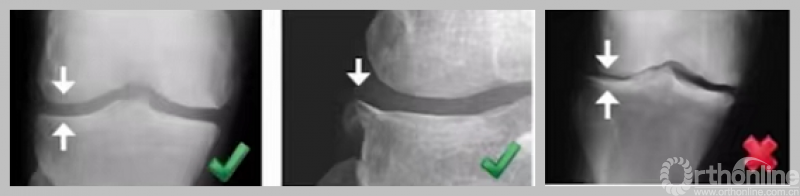

1. 内侧骨关节炎

a.病变位于内侧平台中线以前;b.病变超过平台中线;c.病变触及平台后缘